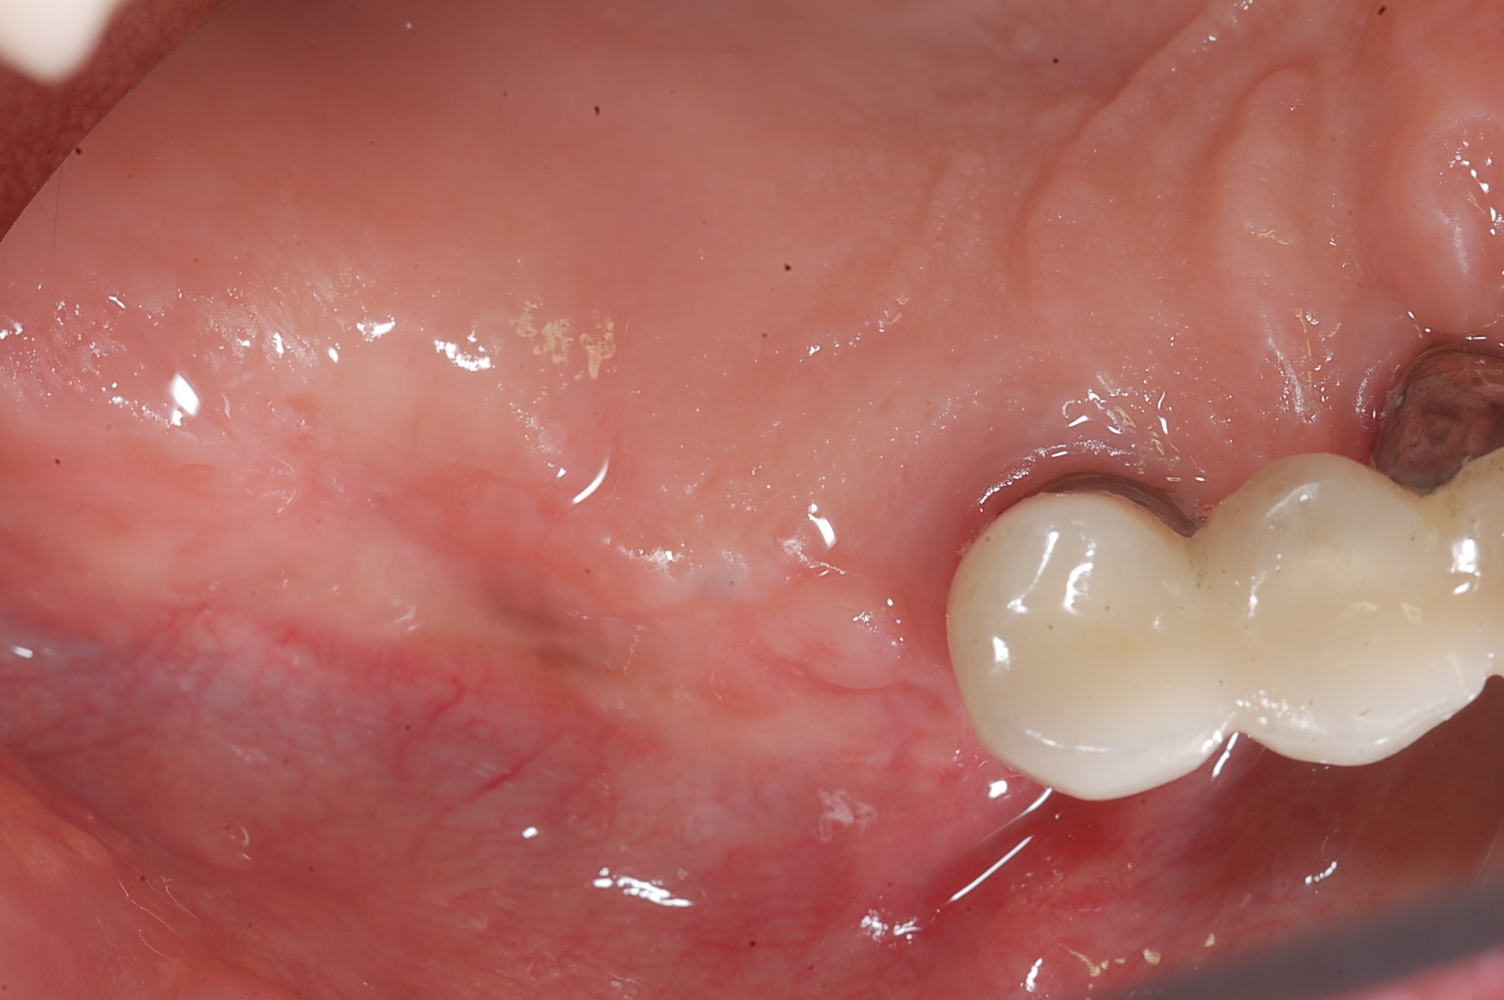

sinus perforation after tooth extraction foundation bone graft PRF kazemi oral surgery 04 Perforation Of Sinus During Tooth Extraction A sinus infection after tooth extraction occurs most commonly when the maxillary molars are removed. If your sinus is perforated from tooth extraction, the tissue normally heals within four to six weeks. Signs of sinus infection after tooth extraction include red, swollen, and inflamed tissue around the perforation, with a discharge of clear yellow. You could have very easily had. Perforation Of Sinus During Tooth Extraction.